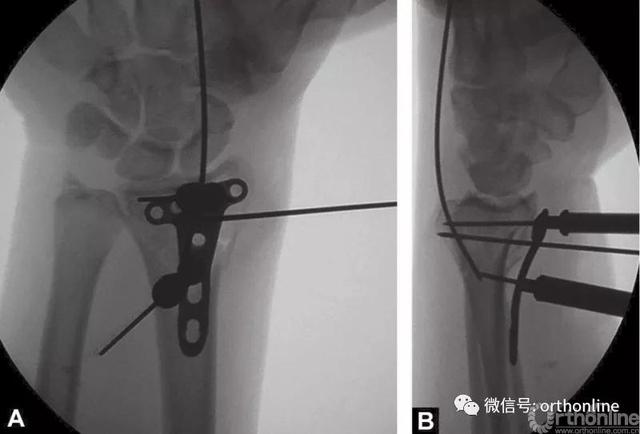

2.4mm桡骨远端T形锁定钢板安放锁定套筒后,置入桡骨远端掌侧面,克氏针通过套筒将钢板临时固定在桡骨远端(图4A和B)。

图4 A和B桡骨远端放置2.4mm锁定钢板和用克氏针临时固定

在软骨下置入远端锁定螺钉能够获得更好的稳定性。X线透视检查钢板放置情况。

远端的锁定螺钉首先置入。接着用一枚普通的2.4mm皮质螺钉置入,将钢板贴向桡骨远端骨面。

由于有远端固定角度的锁定螺钉,钢板紧贴桡骨干能够增加桡骨远端关节面的倾斜度,所以要选用最靠近桡骨干的螺钉孔置入头侧锁定螺钉。